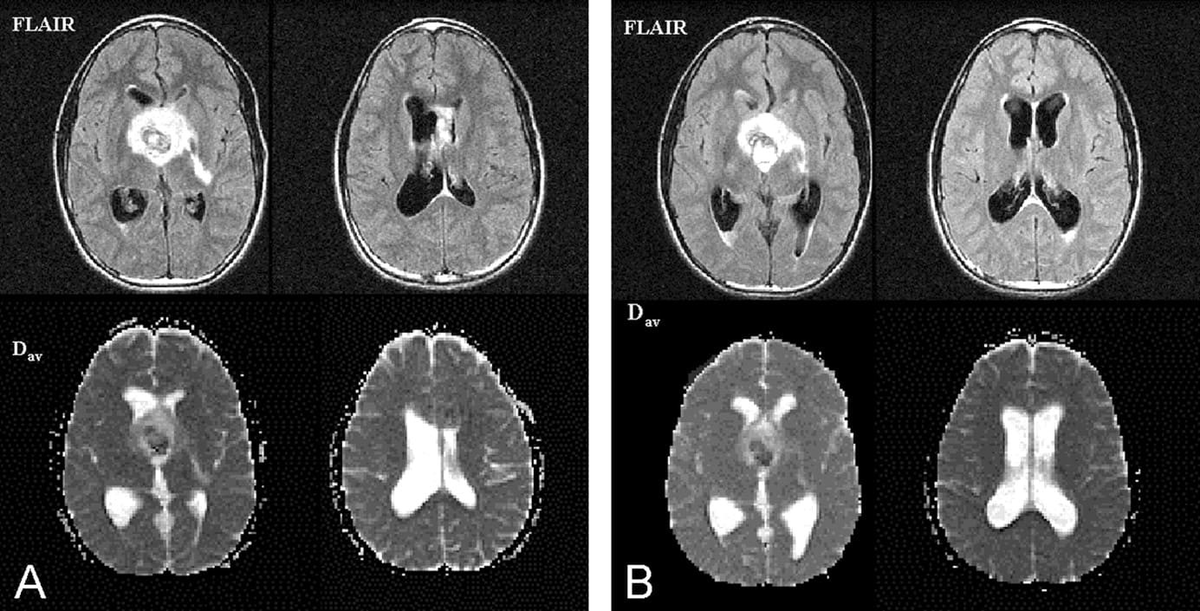

При гидроцефалии наблюдается избыточность этой жидкости с разной степенью выраженности. Иногда эту аномалию еще называют водянкой головного мозга. Неврологи диагноз гидроцефалии ставят на основании конкретных цифр. Например, если по результатам МРТ головного мозга желудочки боковые больше 5 мм - это признак гидроцефалии. Или если на томографии головы наблюдается выраженность борозд коры мозга чуть выше нормы, врач опять же начнет подозревать гидроцефалию. МР-картину наружной заместительной гидроцефалии также подтверждает расширение периваскулярных пространств. Однако следует помнить, что прерогатива постановки окончательного диагноза всегда находится у лечащего врача. Само по себе МРТ обследование головного мозга просто фиксирует состояние органа, и наличие в описании МРТ снимков или в заключении рентгенолога слово гидроцефалия не означает окончательного диагноза.